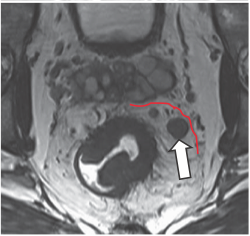

Hình 4. Khối ung thư trực tràng xâm lấn mỡ mạc treo trực tràng

Hình 5. Khối ung thư trực tràng giai đoạn T3 MRF-